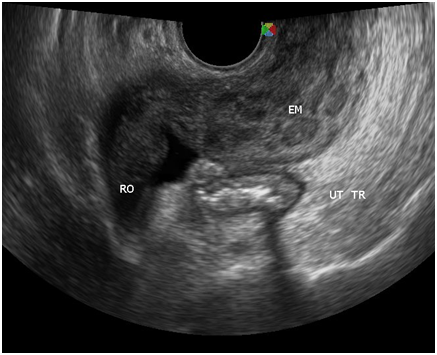

With the four‒month history of rapid abdominal enlargement and significant weight loss, the admitting impression was that of an ovarian new growth probably malignant. However, ultrasound showed only a left adnexal mass described as irregular tubular hyperechoic structure with scattered echogenic stipplings within, densely adherent to the postero‒lateral wall of the uterus, adjacent bowel loops and pelvic sidewalls, while the right ovary appeared grossly normal. Incidentally, there were multiple echogenic foci seen at inferior lobe and parenchyma of the liver, and massive anechoic free fluid was seen in the abdominopelvic cavity. A chest radiograph was also done, which showed pleural effusion on the right; findings suggestive of pulmonary tuberculosis, minimal disease. Work up for tuberculosis was done (Figures 2‒10).

Figure 9 Normal right ovary.

Figure 10 At the left adnexal area is an irregular tubular hyperechoic structure with scattered echogenic stipplings within.

Tuberculous peritonitis is a variant of genital tract tuberculosis. Fallopian tube/uterine disease and tuberculous peritonitis can and does coexist in up to 50% of the cases.22 Tuberculosis is primarily an infection of the respiratory tract. Female genital tuberculosis can develop from a pulmonary nidus of infection or by hematogenous dissemination of organisms and their subsequent localization within the fallopian tube. When the gastrointestinal tract is the portal of infection, involvement of the ileocecal region permits lymphatic spread–primarily to the right fallopian tube.22 The sono graphic findings of this patient described a 5.3x4.6x3.8 cm tubular adnexal mass with scattered echogenic stipplings within, which probably represented tuberculous salpingitis. Myometrial involvement in this patient appeared as irregular scalloping at the periphery of the surrounding hypoechoic myometrium, giving it a marblelized appearance. Dissemination of disease from the fallopian tube occurs by continuous spread to potentially involve the ovary and retrograde into the uterus. Uterine extension involves primarily the endometrium with, at maximum, a 20% incidence of myometrial involvement.22